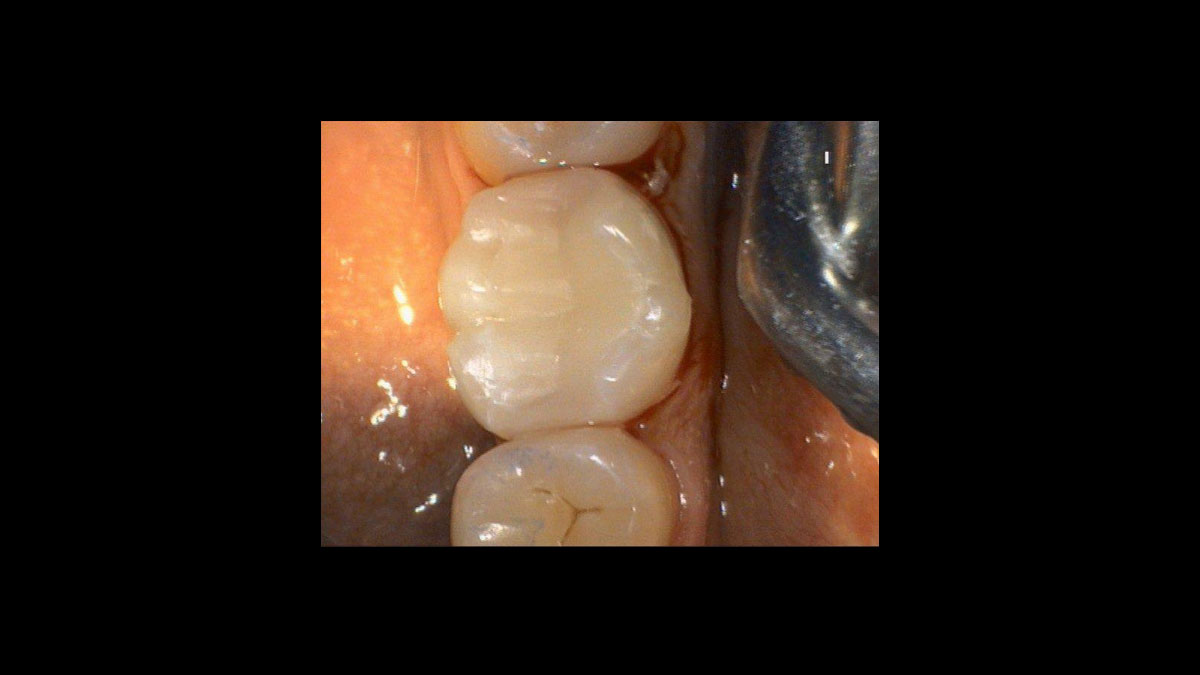

• Implant uncovery

Implant uncovery